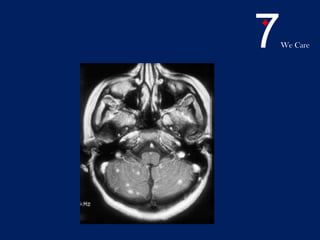

• MRI is the most sensitive test

• superior to CT in detecting parenchymal

abnormalities, such as tuberculomas,

abscesses, and infarctions.